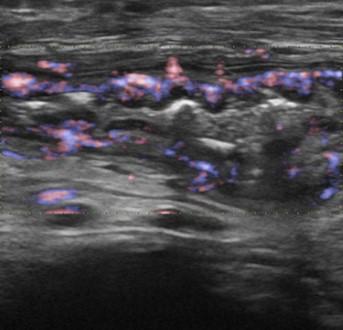

Viêm ruột

» Thông tin: Nữ giới – 55 tuổi.

» Lâm sàng: Tiêu chảy.